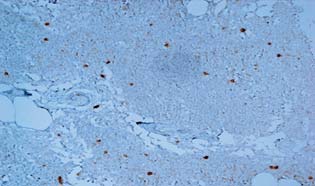

Среднее значение экспрессии АR в ядрах опухолевых клеток пациенток группы люминального подтипа А (57,3±5,9%) было выше по сравнению с экспрессией данного маркёра в группе люминального подтипа B (21,4±4,04%) на 62,7% (р=0,0026). Таким образом, максимальное накопление АR в ядрах опухолевых клеток, которое отмечено у пациенток группы люминального подтипа А, было выше в 2,7 раза (р=0,0023) по сравнению с таковым у пациенток группы люминального подтипа B (рис. 3, 4).

Рис. 3. Низкая экспрессия рецепторов андрогенов в ядрах опухолевых клеток больных люминального подтипа В. Увеличение ×20

Рис. 4. Высокая экспрессия рецепторов андрогенов в ядрах опухолевых клеток больных люминального подтипа A. Увеличение ×20